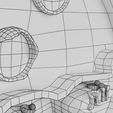

神经肌肉接头示意图